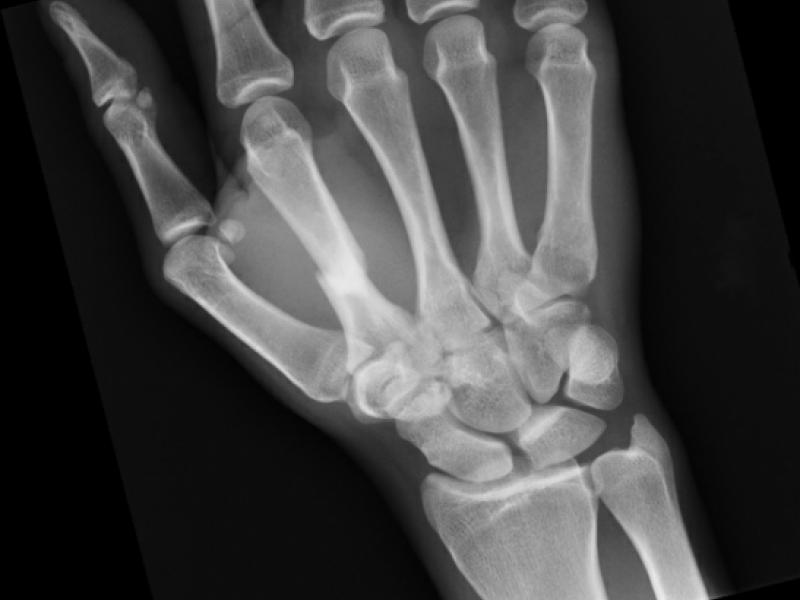

Board Review: Trauma/Orthopedics

50 year old male presenting to the ER with right second and